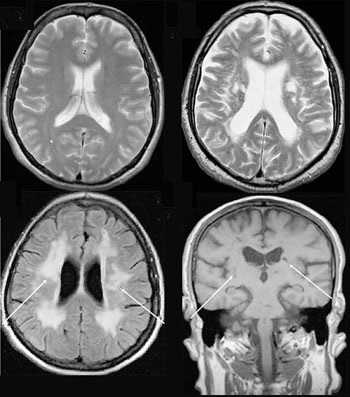

Что показывает МРТ

Магнитно-резонансная томография или МРТ - это сфокусированный метод, который проводит очень детальное обследование. Диагностическая точность МРТ превышает УЗИ и во многих случаях КТ, за исключением сканирования полых органов (легких, желудка, кишечника) и костей. МРТ является золотым стандартом диагностики:

Принцип работы МРТ основан на эффекте ядерного магнитного резонанса. МР томограф в своей конструкции имеет мощный магнит, который создает магнитное поле, и датчик, который подает радиочастотные сигналы. В такой ситуации протоны атомов водорода начинают колебательные движения, выделяя при этом импульсы. Их улавливает компьютер томографа и преобразовывает в трехмерные изображения. Чем больше воды содержится в клетках ткани, тем детальней получается ее изображение. Поэтому на МРТ хорошо отображаются органы с большим содержанием воды: МРТ головного мозга, МРТ спинного мозга, МРТ глазных орбит, МРТ органов малого таза, МРТ позвоночника, МРТ суставов, и плохо визуализируются органы с большим содержанием воздуха МРТ органов грудной клетки или кости.

В основе МРТ лежит явление магнитного резонанса, основанного на переизлучении радиоволн, взаимодействующих с атомами водорода, в избытке содержащимися в организме человека. Эти переизлученные электромагнитные волны улавливаются датчиком МР-томографа, усиливаются и в виде цифровых изображений появляются на экране монитора. Это безвредный и абсолютно безопасный для здоровья человека метод лучевой диагностики, так как в основе получения изображения отсутствует рентгеновское излучение, поэтому МРТ можно проходить неограниченное количество раз, с любым интервалом.

Существенное преимущество МР-томографии перед КТ заключается в том, что она не противопоказана беременным во II и III триместре и совершенно безопасна для детей. В МРТ исследуемая область сканируется в трех проекциях, что позволяет врачу-рентгенологу в полной мере оценить состояние тканей и органов исследуемой области, а высокая контрастность изображения и пространственное разрешение позволяют визуализировать серое и белое вещество головного мозга, оценивать состояние костного мозга и мягких тканей различной локализации. Кроме того, метод МРТ позволяет получать изображения сосудов головного мозга и сосудов шеи без введения контрастного препарата.

Мы также всегда делаем КТ пациентам с подозрением на нарушение мозгового кровообращения, исследование позволяет не только подтвердить диагноз, но и оценить «масштаб» поражения и выработать верную тактику. Назначают его при патологии почек, в частности, при наличии камней. На томографе можно увидеть их расположение, оценить плотность и структуру, а значит, принять решение об операции или выборе консервативных методов. МРТ имеет преимущества при изучении патологий суставов, для диагностики заболеваний головного мозга, спинного мозга, органов малого таза.

Есть некоторые органы, обследование которых рекомендуют начинать с проведения МРТ. В частности, речь идет о головного мозге. С помощью УЗИ оценить его строение у взрослых очень проблематично, т. к. со всех сторон мозг заключен в череп, который практически не пропускает ультразвуковых волн. Для МРТ это не является препятствием.